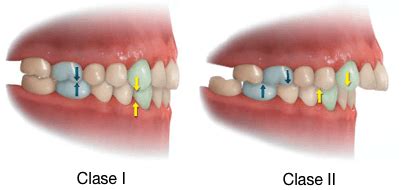

Este artículo presenta el caso clínico de una paciente adulta con ausencias y agencias que es tratada con aparatología ortodóncica fija multibrackets previamente a la rehabilitación protésica sobre implantes. La paciente presenta severas desviaciones de líneas medias dentales y oclusión asimétrica en clase II canina derecha y clase III izquierda.

Tiene oclusión en clase II canina derecha de 4,5 mm, ausencia del canino superior izquierdo y clase III izquierda de 7,5 mm del primer premolar (adyacente al pórtico del incisivo lateral) con el canino inferior izquierdo. Discrepancia óseo-dentaria inferior de 8 mm y superior de 5 mm negativos. Morfología craneofacial normal.

La línea media superior está desviada hacia la izquierda de la paciente debido a la ausencia de un diente anterior en el segundo cuadrante. Por la misma causa la paciente presenta clase III canina izquierda. Tiene desviación de la línea media inferior hacia la derecha con clase II canina y premolar. Los caninos inferiores están vestibulizados en posición no funcional.

- Se consigue el centrado de la línea media superior y la oclusión en clase I canina bilateral clase II molar completa bilateral, proporcionando a la paciente guía canina bilateral.